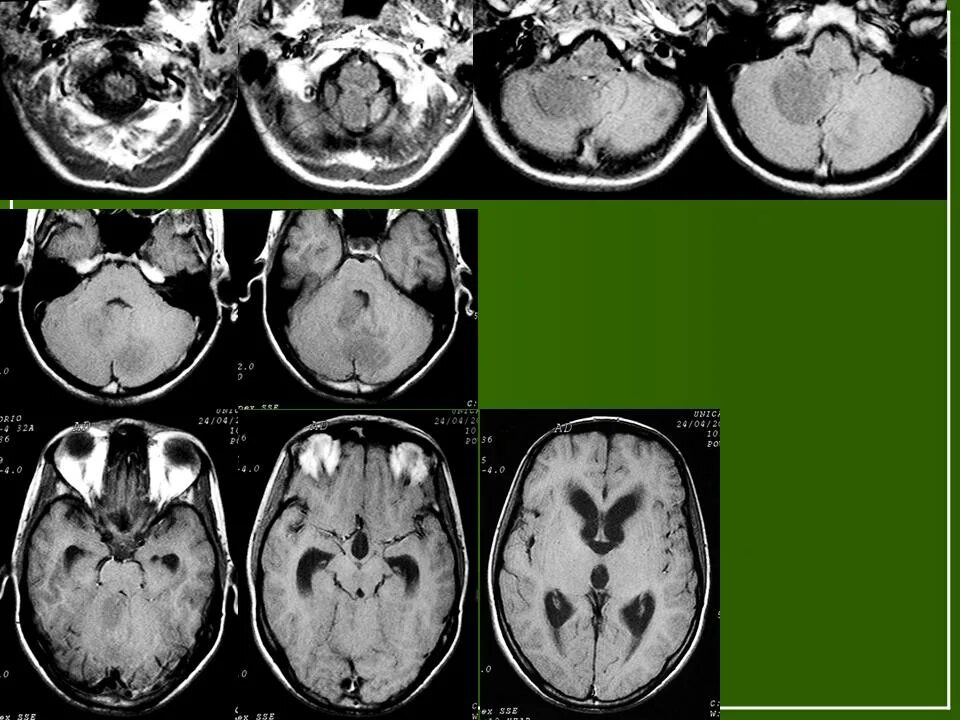

Медуллобластома это